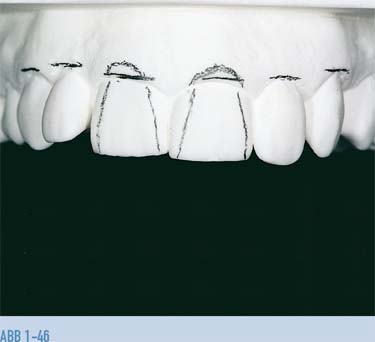

Abb. 1-46 Korrektur auf dem Gipsmodell.

Abb. 1-47 und 1-48 Nach einer Modellgingivektomie wird die ideale Position des Gingivaverlaufs und die neue zervikale Ausdehnung der Kronen am Modell mit einem Bohrer ausgeformt und das diagnostische Wax-up mit dem Ziel fertig gestellt, das ideale ästhetische Ergebnis, wie es dem Patienten vorgeschlagen wurde, in Wachs zu reproduzieren. Die Form und Anatomie der Zähne wurden vom Techniker so geplant, dass die Dominanz der zentralen Schneidezähne wieder hergestellt wurde.